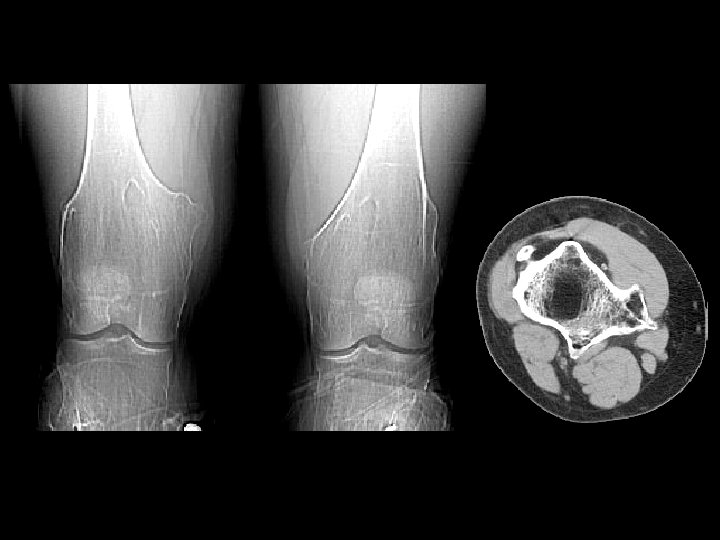

Aneurysmal bone cyst • Findings: – Lucent end of bone lesion in the proximal tibia – Slightly expansile, mild periosteal reaction – Fluid-fluid level on MRI • ddx: – Giant cell tumor – Unicameral bone cyst – Fibrous dysplasia – Chondroblastoma (rare)